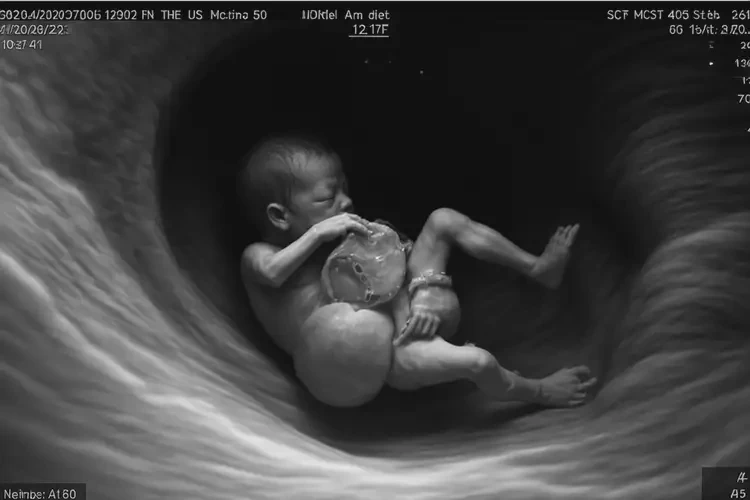

孕31周胎心170多寶寶還能要嗎(圖1)